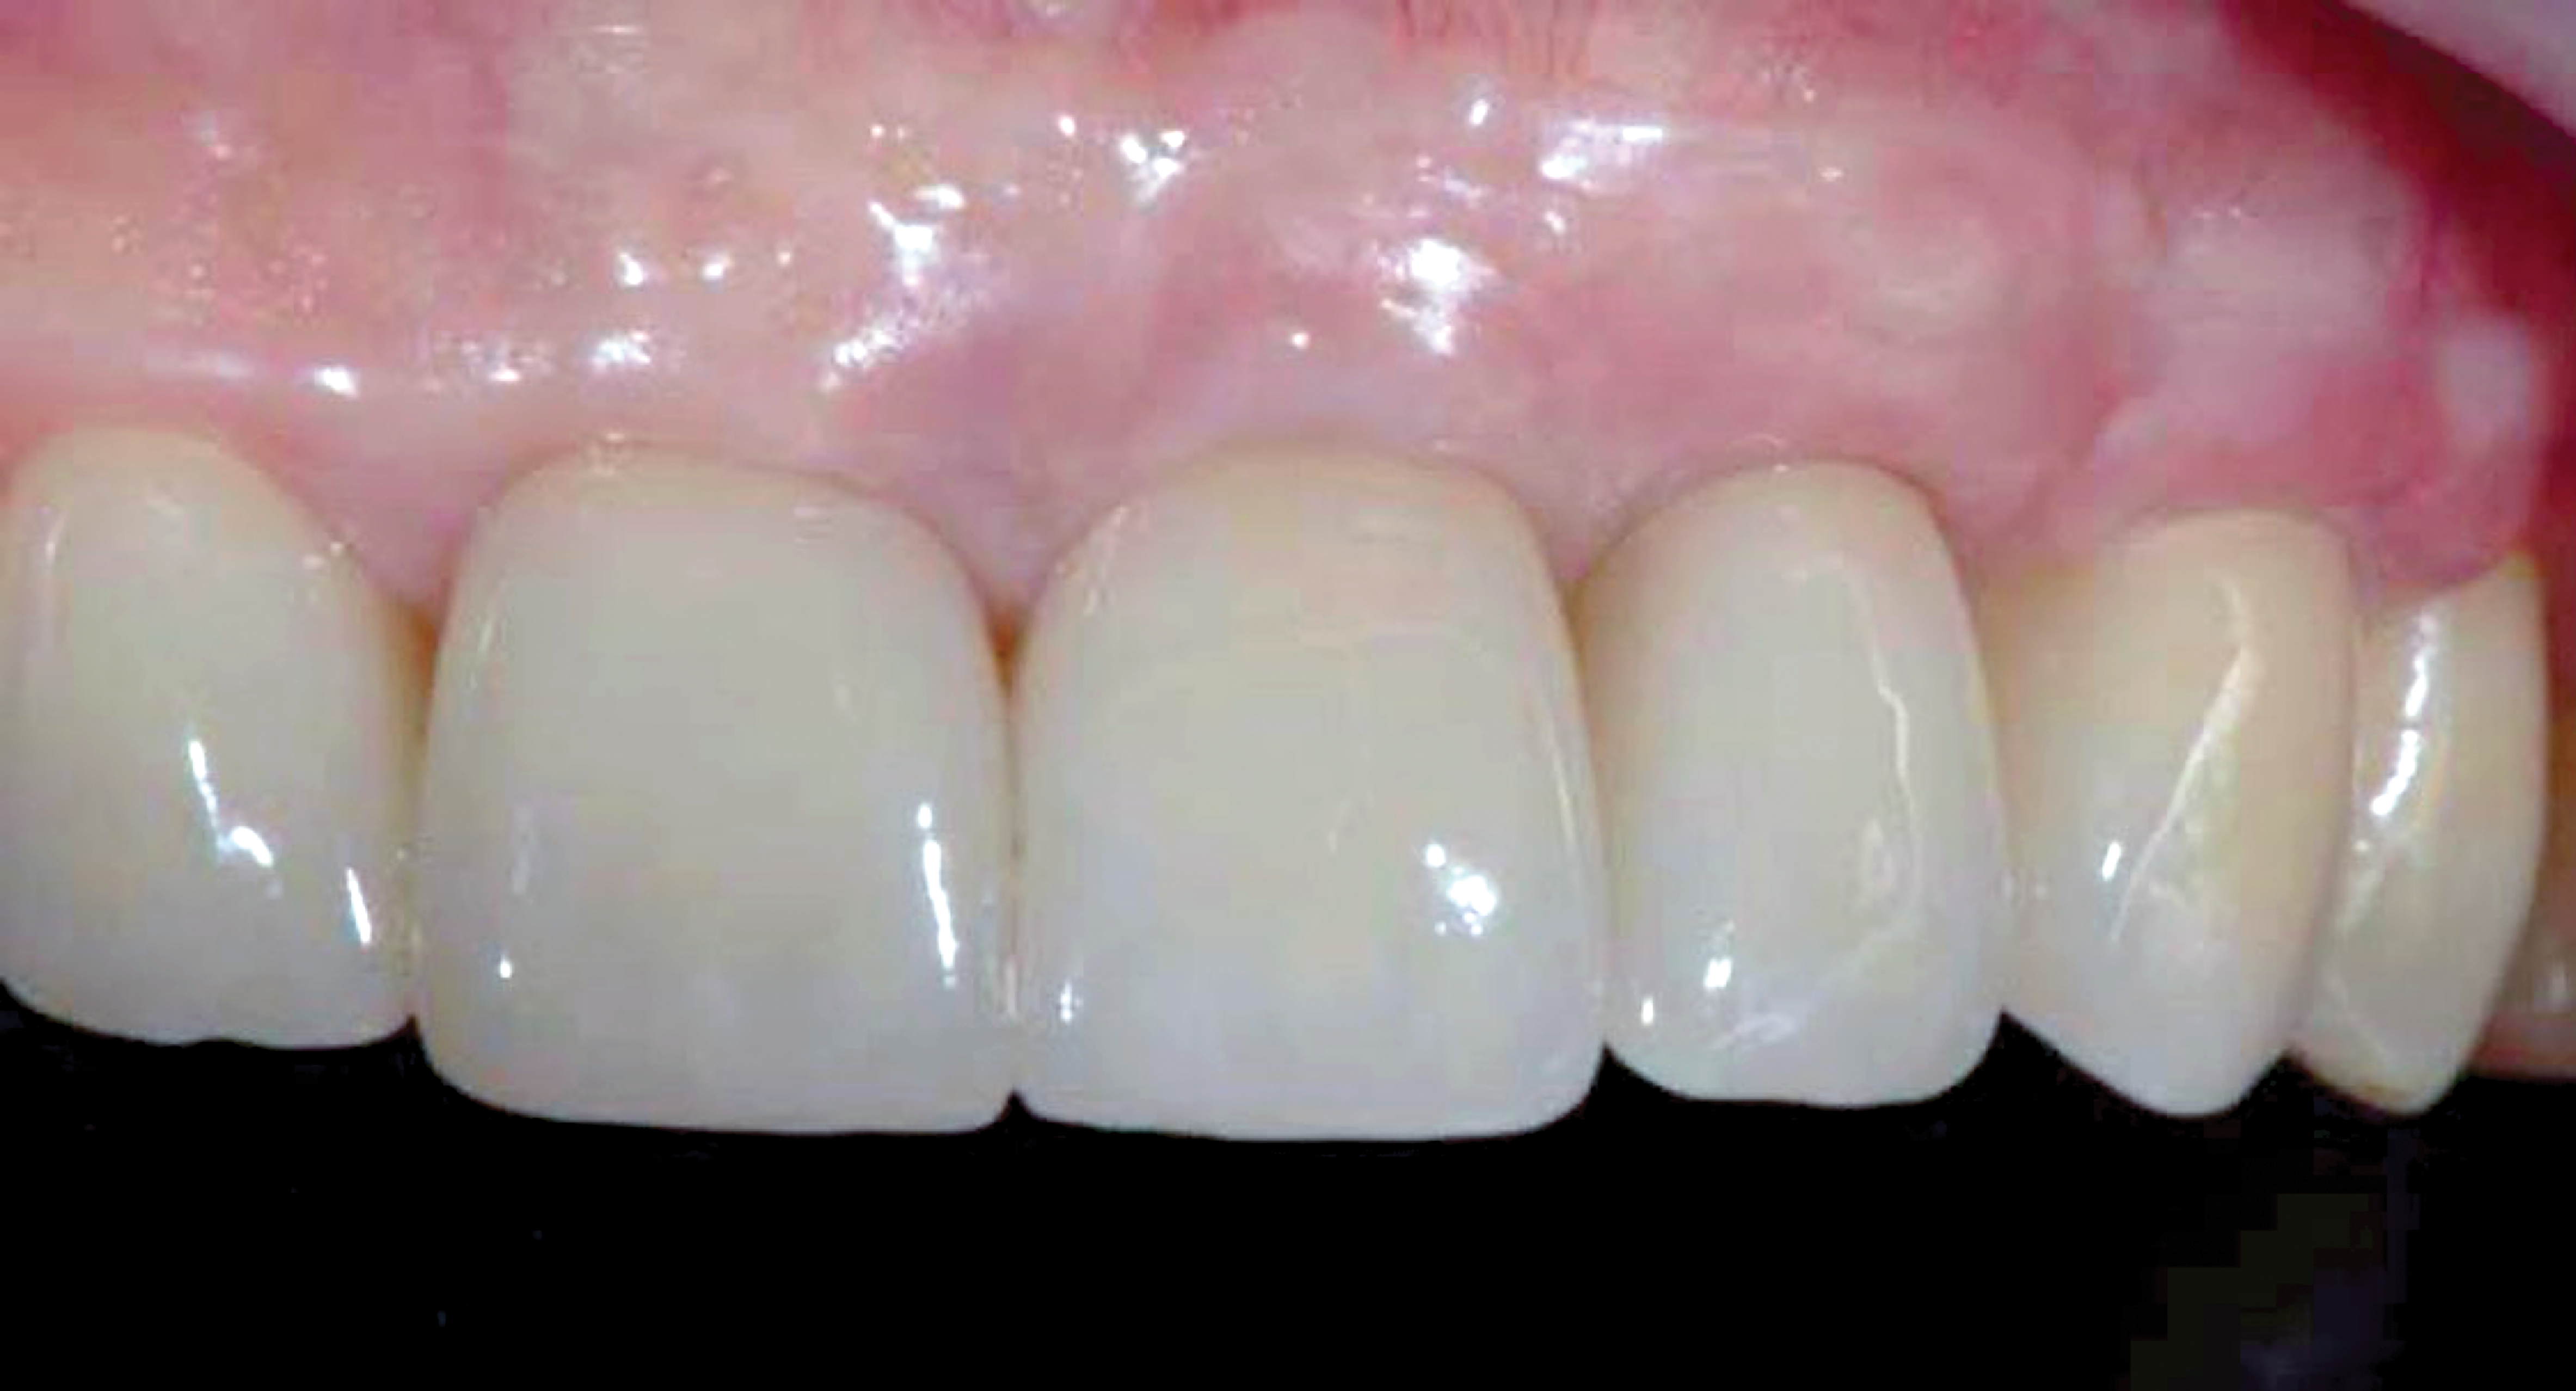

Fig 1. Frontal clinical view at baseline.

Figure 1

After 3 months of healing, the second-stage procedure was performed to uncover the dental implants. Then, after 6 months of soft-tissue conditioning with temporary crowns, the case was completed with permanent, implant-supported restorations (Figure 16 and Figure 17).

Fig 16. Final clinical outcome at 12 months post–iCTG augmentation.

Figure 16